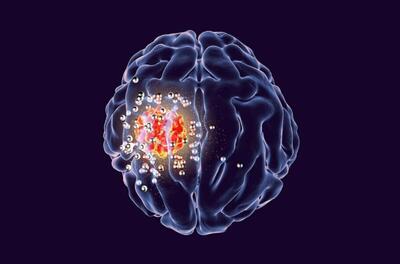

اشعه ایکس با دوز پایین میتواند سلولهای تومور مغزی را نابود کند!

پروفسور Pu Kanyi نویسنده ارشد و همکار این مطالعه گفت: «ما از دوزهای بسیار پایین اشعه ایکس و MRAPهای کشنده سرطان استفاده کردیم.